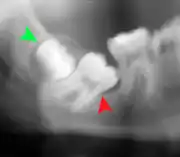

Impacted wisdom tooth with a backward tilt (distoangular impaction) and chronic infection to back of crown (green arrow)

Panoramic radiograph of impacted lower wisdom teeth (green arrows) in a 26-year-old with dental caries (red arrows) on the adjacent teeth

The diagnosis of impaction can be made clinically if enough of the wisdom tooth is visible to determine its angulation, depth, and if the patient is old enough that further eruption or uprighting is unlikely. Wisdom teeth continue to move to the age of 25 years old due to eruption, and then continue some later movement owing to periodontal disease.[18]

If the tooth cannot be assessed with clinical exam alone, the diagnosis is made using either a panoramic radiograph or cone-beam CT. Where unerupted wisdom teeth still have eruption potential several predictors are used to determine the chance of the teeth becoming impacted. The ratio of space between the tooth crown length and the amount of space available, the angle of the teeth compared to the other teeth are the two most commonly used predictors, with the space ratio being the most accurate. Despite the capacity for movement into early adulthood, the likelihood that the tooth will become impacted can be predicted when the ratio of space available to the length of the crown of the tooth is under 1.[5]:141

Impacted 2nd molar (red arrow) with developing wisdom tooth (green arrow)

There is no standard to screen for wisdom teeth. It has been suggested, absent evidence to support routinely retaining or removing wisdom teeth, that evaluation with panoramic radiograph, starting between the ages of 16 and 25 be completed every 3 years. Once there is the possibility of the teeth developing disease, then a discussion about the operative risks versus long-term risk of retention with an oral and maxillofacial surgeon or other clinician trained to evaluate wisdom teeth is recommended. These recommendations are based on expert opinion level evidence.[19] Screening at a younger age may be required if the second molars (the "12-year molars") fail to erupt as ectopic positioning of the wisdom teeth can prevent their eruption. Radiographs can be avoided if the majority of the tooth is visible in the mouth.